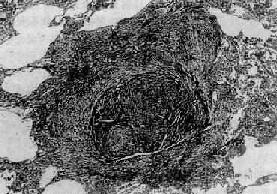

图9-12 腺泡中央型肺气肿

呼吸细支气管呈囊状扩张,伴行肺动脉(径80μm)管壁增厚,其分支内膜增厚,管腔极度狭窄